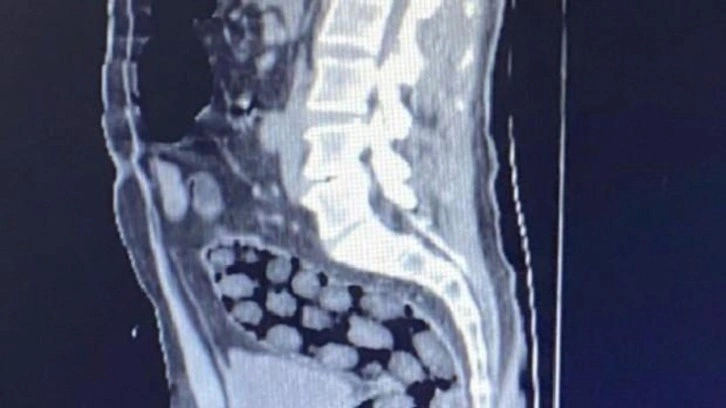

Bitlis Valiliğinden yapılan açıklamada,  uyuşturucu ile mücadele kapsamında elde edilen istihbari bilgiler doğrultusunda Tatvan’da durdurulan bir otobüste yabancı uyruklu 3 yolcunun yakalandığı belirtildi. Açıklamada, “Bitlis Emniyet Müdürlüğü Narkotik Suçlarla Mücadele Şube Müdürlüğü ve İstihbarat Şube Müdürlüğü ekiplerince gözaltına alınan ve Tatvan Devlet Hastanesine sevk edilen şüphelilerin röntgen ve tomografi görüntülerinde mide ile bağırsaklarında çok sayıda yabancı cisim bulunduğu tespit edilmiş, yapılan tıbbi müdahale ile şüphelilerin  paketleyerek yuttuğu toplam 91 adet daralı ağırlığı 1 kilo 126 gram metamfetamin maddesine el konulmuştur. Şüpheliler, çıkarıldığı adli mercilerce tutuklanarak cezaevine gönderilmiştir. Hemşehrilerimizin huzuru ve güvenliği için uyuşturucu madde imalatı, kaçakçılığı ve kullanımına karşı yürütülen kararlı mücadelemiz devam edecektir” denildi.